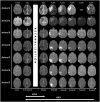

Although early diffusion lesion reversal after recanalization treatment of acute ischaemic stroke has been observed in clinical settings, the reversibility of lesions observed by diffusion-weighted imaging remains controversial. Here, we present consistent observations of sustained diffusion lesion reversal after transient middle cerebral artery occlusion in a monkey stroke model. Seven rhesus macaques were subjected to endovascular transient middle cerebral artery occlusion with in-bore reperfusion confirmed by repeated prospective diffusion-weighted imaging. Early diffusion lesion reversal was defined as lesion reversal at 3 h after reperfusion. Sustained diffusion lesion reversal was defined as the difference between the ADC-derived pre-reperfusion maximal ischemic lesion volume (ADCD-P Match) and the lesion on 4-week follow-up FLAIR magnetic resonance imaging. Diffusion lesions were spatiotemporally assessed using a 3-D voxel-based quantitative technique. The ADCD-P Match was 9.7 ± 6.0% (mean ± SD) and the final infarct was 1.2-6.0% of the volume of the ipsilateral hemisphere. Early diffusion lesion reversal and sustained diffusion lesion reversal were observed in all seven animals, and the calculated percentages compared with their ADCD-P Match ranged from 8.3 to 51.9% (mean ± SD, 26.9 ± 15.3%) and 41.7-77.8% (mean ± SD, 65.4 ± 12.2%), respectively. Substantial sustained diffusion lesion reversal and early reversal were observed in all animals in this monkey model of transient focal cerebral ischaemia.